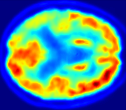

Looking at sample synthetic PET images in Fig. 3, it can be seen that all of the models are able to make reasonable predictions. The outputs of the U-PET and U-PET (no att.) look very similar and are smoothed compared to the input. The pix2pix predicts more details, which seem to be important for the discriminator. However, even though this model has finer predictions, the intensity values are worse compared to the U-PET and U-PET (no att.) as seen in Fig. 2; an example is given in Fig. 3 in the second row.

From a clinical perspective, the synthetic generated PET show a smoother version of the real PET images but keep the same pattern of FDG uptake, especially, hypometabolism in the respective brain areas. This backs up our hypothesis, that MRI contains information that correlates with the functional information of PET images. Moreover, the synthetic PET could be used as complementary visualization for physicians beyond the task of classification.

| MRI | PET | Synthetic PET | AttMap skip | AttMap |

In Fig. 4, the attention maps of the U-PET are shown for multiple examples. On the one hand, the attention map of the skip connection (AttMap skip) highlights details of the brain structure, which is in agreement with the assumption that the network has to transform the specific structures of the MRI scan into the PET modality. On the other hand, the attention gates used for the classification task rather focus on more specific regions. One can observe a trend that the attention maps used for classification tend to highlight regions which have a low uptake in the PET. Since areas with a lower uptake in the PET correspond to areas with lower functional activity (hypometabolism), this focus area of the network seems reasonable with respect to the classification task.